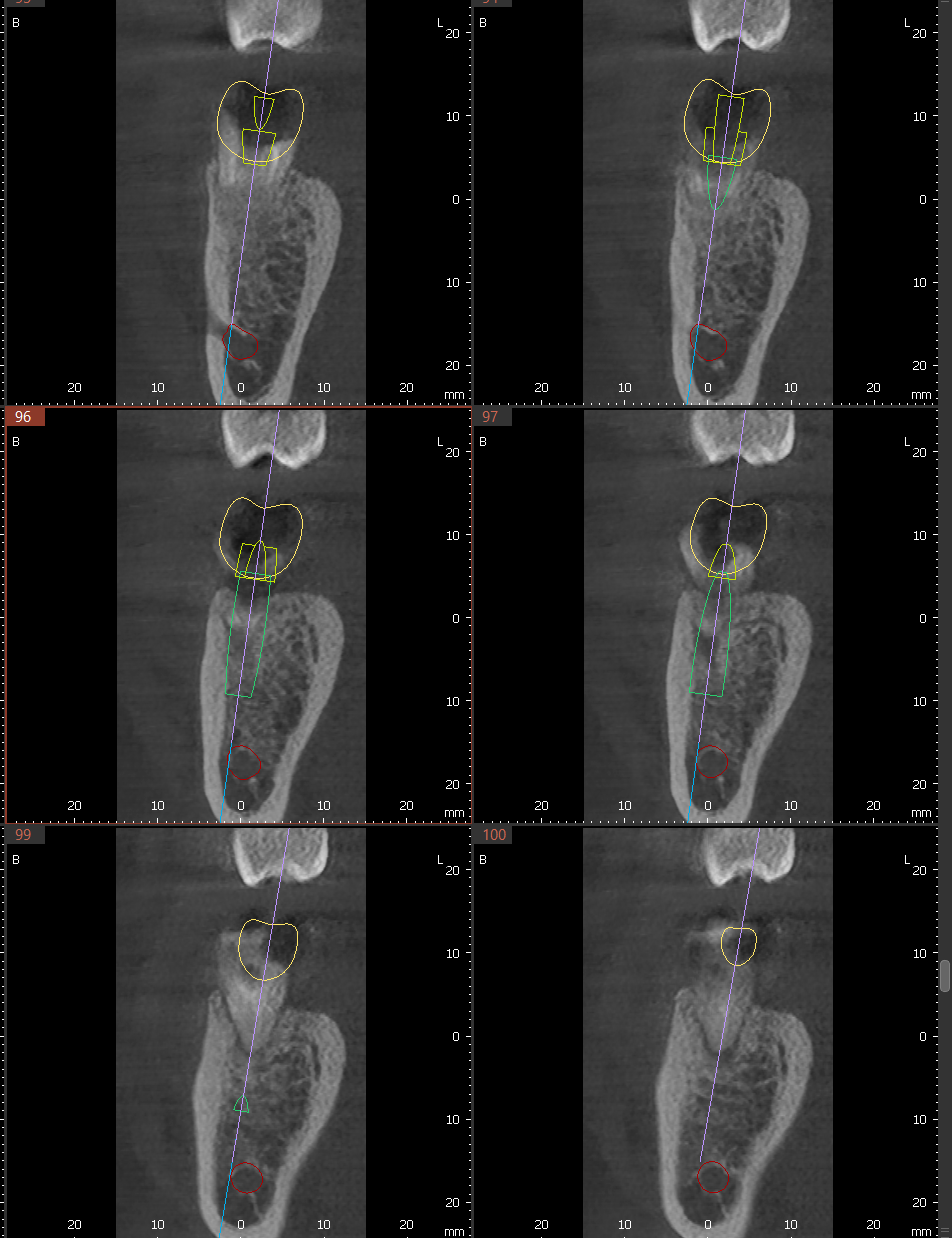

- 3D ENDO: Snimanje manje regije (npr. dva do tri zuba).

Vidljivost bez preklapanja: Otkriva anatomske detalje (poput dodatnih kanala korena) koji su na standardnim snimcima često skriveni.

- Endodoncija (3D ENDO): Precizna analiza kanala korena i upalnih procesa.

- Trodimenzionalna slika korenskih kanala, otkriva skrivene kanale i periapikalne lezije koje 2D snimak ne može prikazati.Polje snimanja od svega 5×5 cm znači ciljanu dijagnostiku. Snimak je gotov za manje od 10 minuta, uz AI asistenciju i digitalnu dostavu — bez zakazivanja.